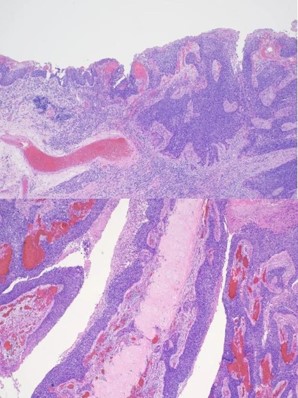

The patient was seen in an outpatient setting for a two week follow-up and discussion of final pathology results. These showed two masses: ameloblastoma with the invasion of the hard palate, posterior maxilla, and maxillary sinus (Figure 5) as well as a SCC with the cartilaginous and bony invasion of the nasal septum and nasal bone (Figure 6). During this clinic visit, he reported some discharge from one of the incisions and flap edema. He was otherwise doing well, with significant improvements in dysphagia and nasal obstruction. The flap adhered well to native tissue and appeared healthy. The infection cleared up over the next two weeks on a course of antibiotics, and the patient’s nasogastric tube was removed within the following three weeks.

Figure 6: Photomicrograph demonstrating moderately differentiated squamous cell carcinoma.

We report a case of extensive nasal bone, hard palate, and sinus invasion from squamous cell carcinoma, which muddied the identification of an ameloblastoma. Simultaneous occurrences of ameloblastomas and SCC are rare, and it is difficult to appreciate both entities during initial examination. The ameloblastoma was present along the left maxillary sinus, posterior maxilla, and hard palate. Where moderately differentiated keratinizing squamous cell carcinoma was seen along the nasal bone and septal cartilage. In this case, metastatic disease was not found, and the margins were negative. The pathological staging was pT3N0M0 and pT4N0M0 for the ameloblastoma and squamous cell carcinoma, respectively. He was referred to radiation oncology and recommended to proceed with radiation therapy, but the patient opted not to pursue it. Previous case reports discuss the radiosensitivity of squamous cell carcinoma and the uncertainness of the role of radiation therapy in ameloblastomas [5,6].